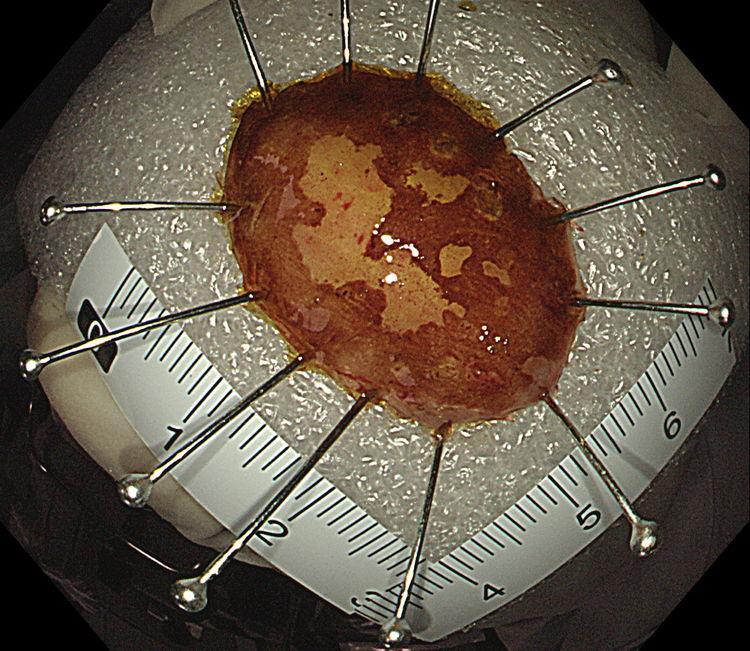

术后标本卢戈碘染示:病灶完整剥离

术后病理示:食管黏膜原位癌